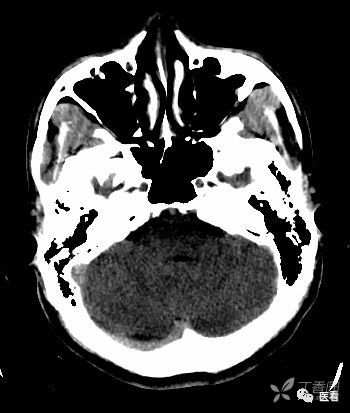

亨氏暗区

颅底(致密)骨产生的横行或放射状伪影,与设备性能也有关系

下图为16拍MSCT,伪影较轻。

此图为双排螺旋 CT图像, 伪影较16层及以上MSCT显著的多。